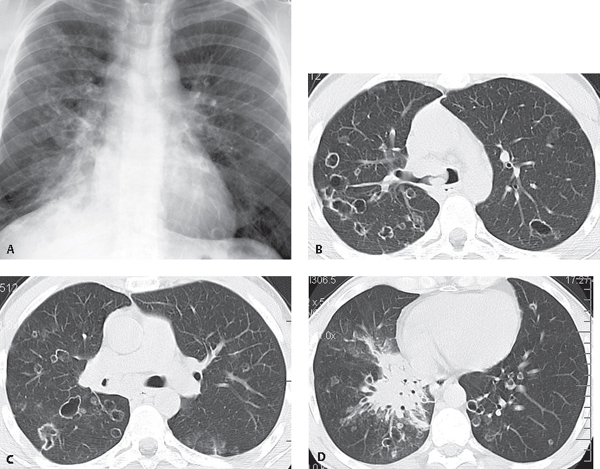

Визуализация и диагностика неинвазивного аспергиллеза с помощью КТ

Раздел: Необычные решения